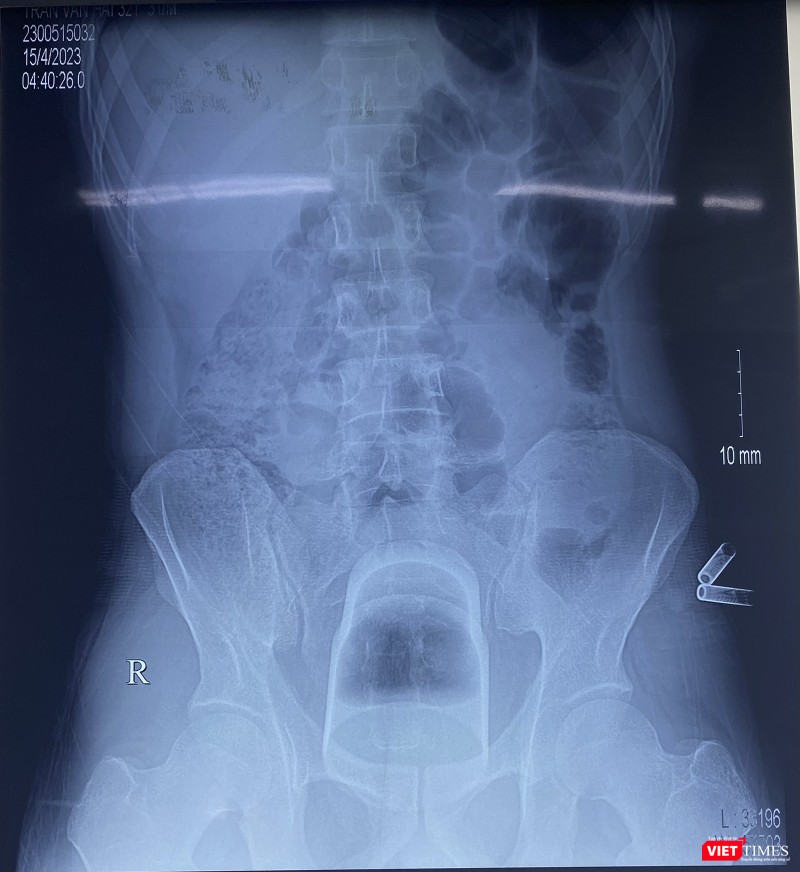

"Kết quả phim chụp X-quang phát hiện dị vật nằm sâu trong trực tràng của bệnh nhân. Do dị vật có kích thước lớn, lại nằm rất sâu trong trực tràng và kẹt chặt vào khung chậu nên không thể lấy được qua đường hậu môn. Các bác sĩ quyết định mổ mở trực tràng để lấy dị vật và đưa đại tràng sigma ra ngoài làm hậu môn nhân tạo”- BS Phạm Hiếu Tâm cho biết.

| Phim X-quang chiếc cốc đánh răng nằm sâu trong trực tràng của bệnh nhân (ảnh BVCC) |